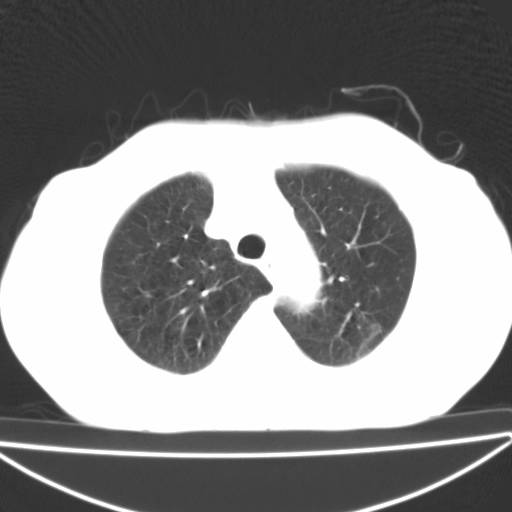

以下是引用zjzjr在2006-12-6 19:04:00的发言:[br]左肺上叶尖后段可见椭圆形高密度影,其内可见点状钙化影,周围可见卫星病灶.首先考虑结核,双侧少量胸腔积液.

以下是引用李世军在2006-12-6 19:54:00的发言:[br]左肺上叶尖后段可见椭圆形高密度影,其内可见点状钙化影,周围可见卫星病灶.首先考虑结核,双侧少量胸腔积液. [br] [br] 双肺轻度肺气肿,左肺上叶后段见多发斑片状密度增高影,周围见少许斑点状卫星病灶,双侧胸膜增厚粘连,纵隔内未见明显改变,考虑结核可能性大,请结合临床或增强扫描. [br] [br]

以下是引用13081830109在2006-12-6 19:35:00的发言:[br]左肺上叶尖后段可见椭圆形高密度影,其内可见点状钙化影,周围可见卫星病灶.首先考虑结核,双侧少量胸腔积液.

以下是引用守望可可西里在2006-12-7 0:01:00的发言:[br][quote]以下是引用zjzjr在2006-12-6 19:04:00的发言:[br]左肺上叶尖后段可见椭圆形高密度影,其内可见点状钙化影,周围可见卫星病灶.首先考虑结核,双侧少量胸腔积液.